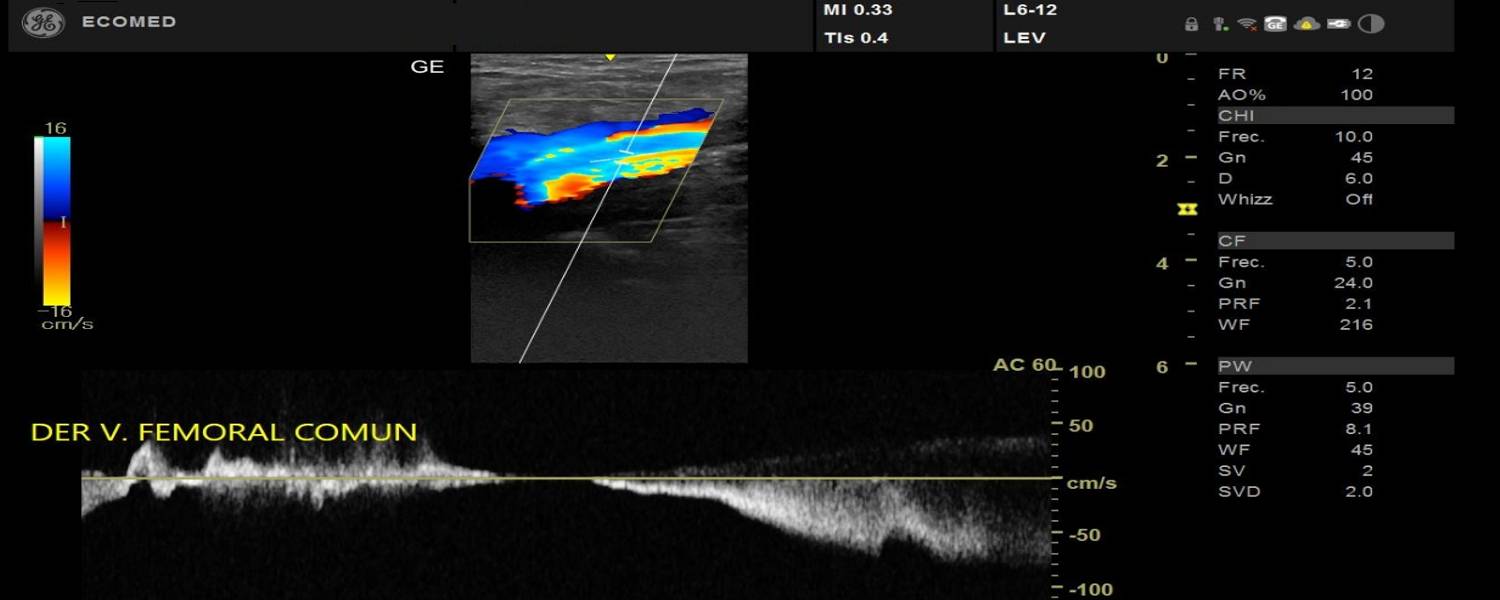

Una ecografía es un examen médico que uiliza un transductor para capturar imágenes en vivo desde el interior de su cuerpo mediante ondas sonoras de alta frecuencia.

La ecografía le permite al médico ver problemas con órganos, tejidos y vasos sin necesidad de efectuar una incisión.